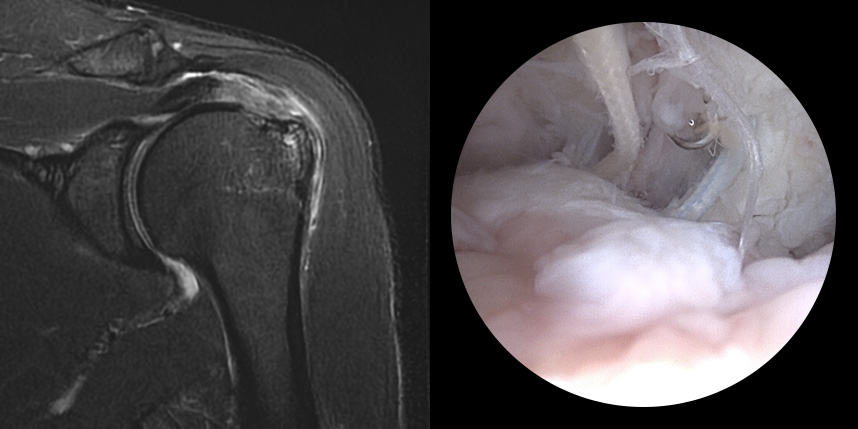

MRI상 회전근개 파열이

진행되는 경우

완전 파열시

브릿지 봉합술